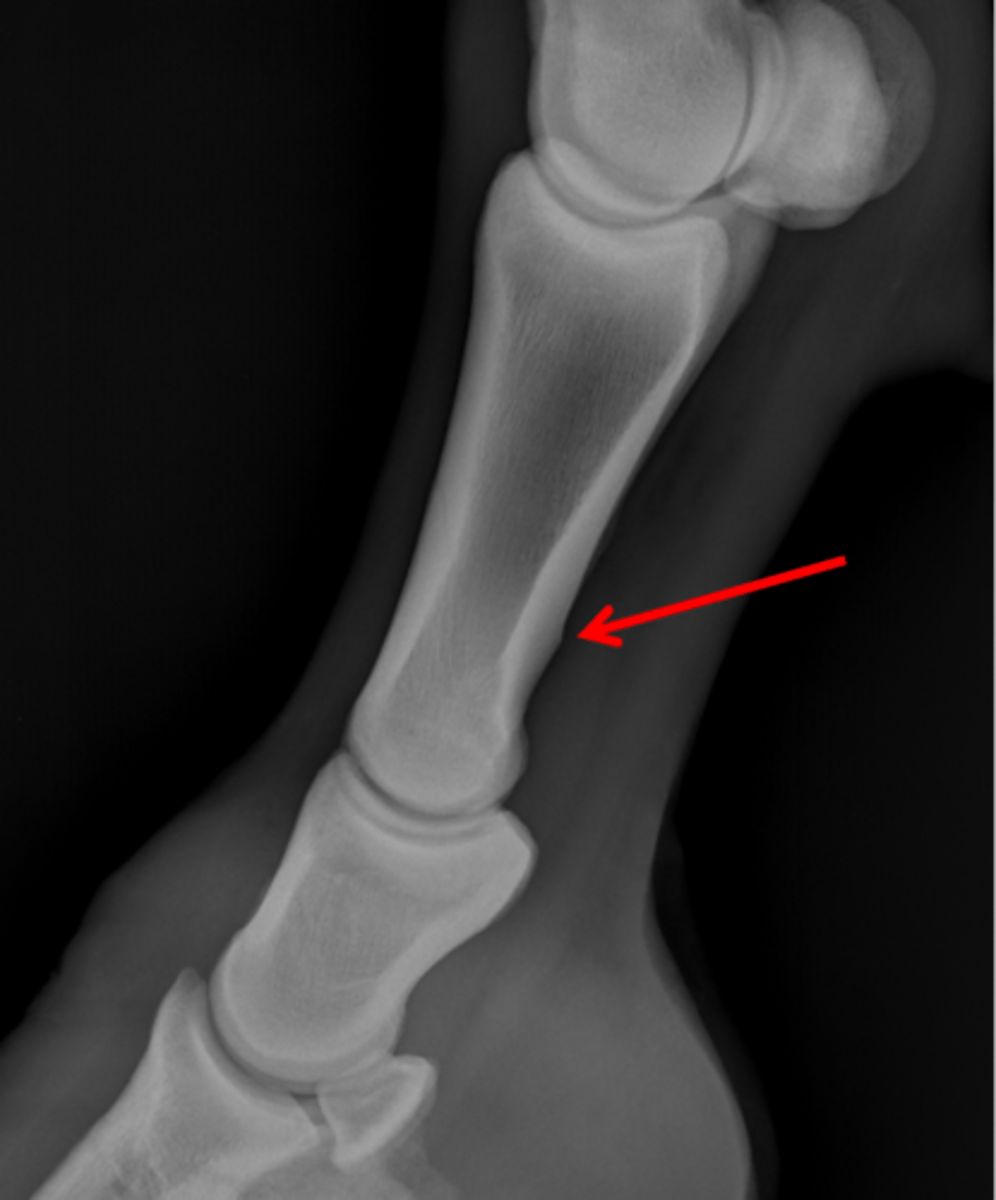

Short pastern (P2)

Upright pedal or high coronary

What view is this?

Short pastern (P2)

Long pastern (P1)

Long pastern (P1)

Short pastern (P2)

Medullary cavity

Ergot

Nutrient foramen of P2